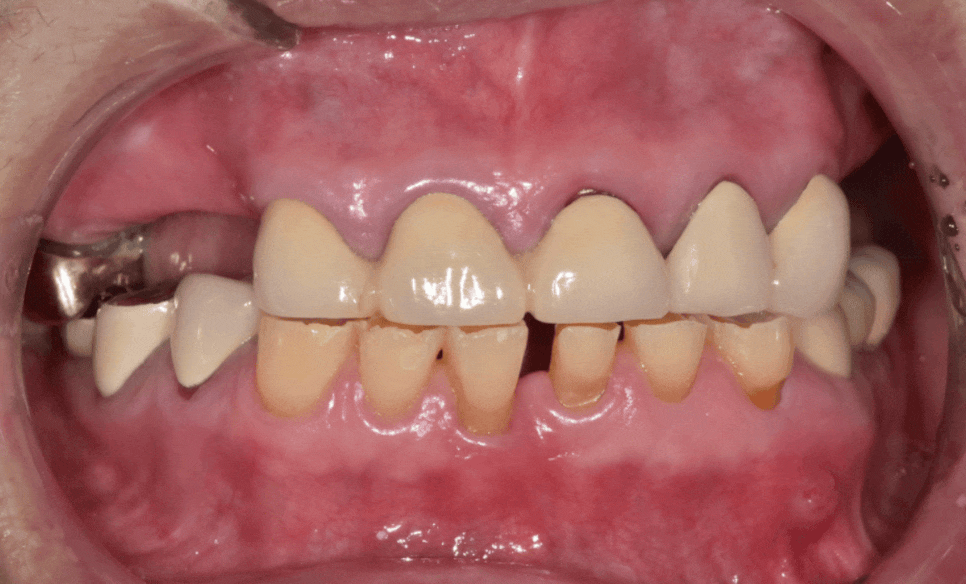

이 환자분은 오랜 시간 동안 치아가 많이 닳아,

전체적으로 치아가 낮아진 상태였습니다.

230211

입안을 보니

앞니뿐 아니라 어금니까지 평평하게 닳아 있었고,

오른쪽 아래 임플란트 보철이

유난히 낮게 제작되어 있었습니다.

위쪽 앞니 5개는 상황이 달랐습니다.

여러 개가 하나의 보철(브리지)로 묶여 있었는데,

이를 제거해 보니

230715

안쪽 치아들은 많이 상해 있었고 남아 있는 치아 자체도 너무 작았습니다.

이 상태로 다시 씌운다고 해도

보철이 오래 버티기 어려운 상태였습니다.

230211 (전) 240510 (후)